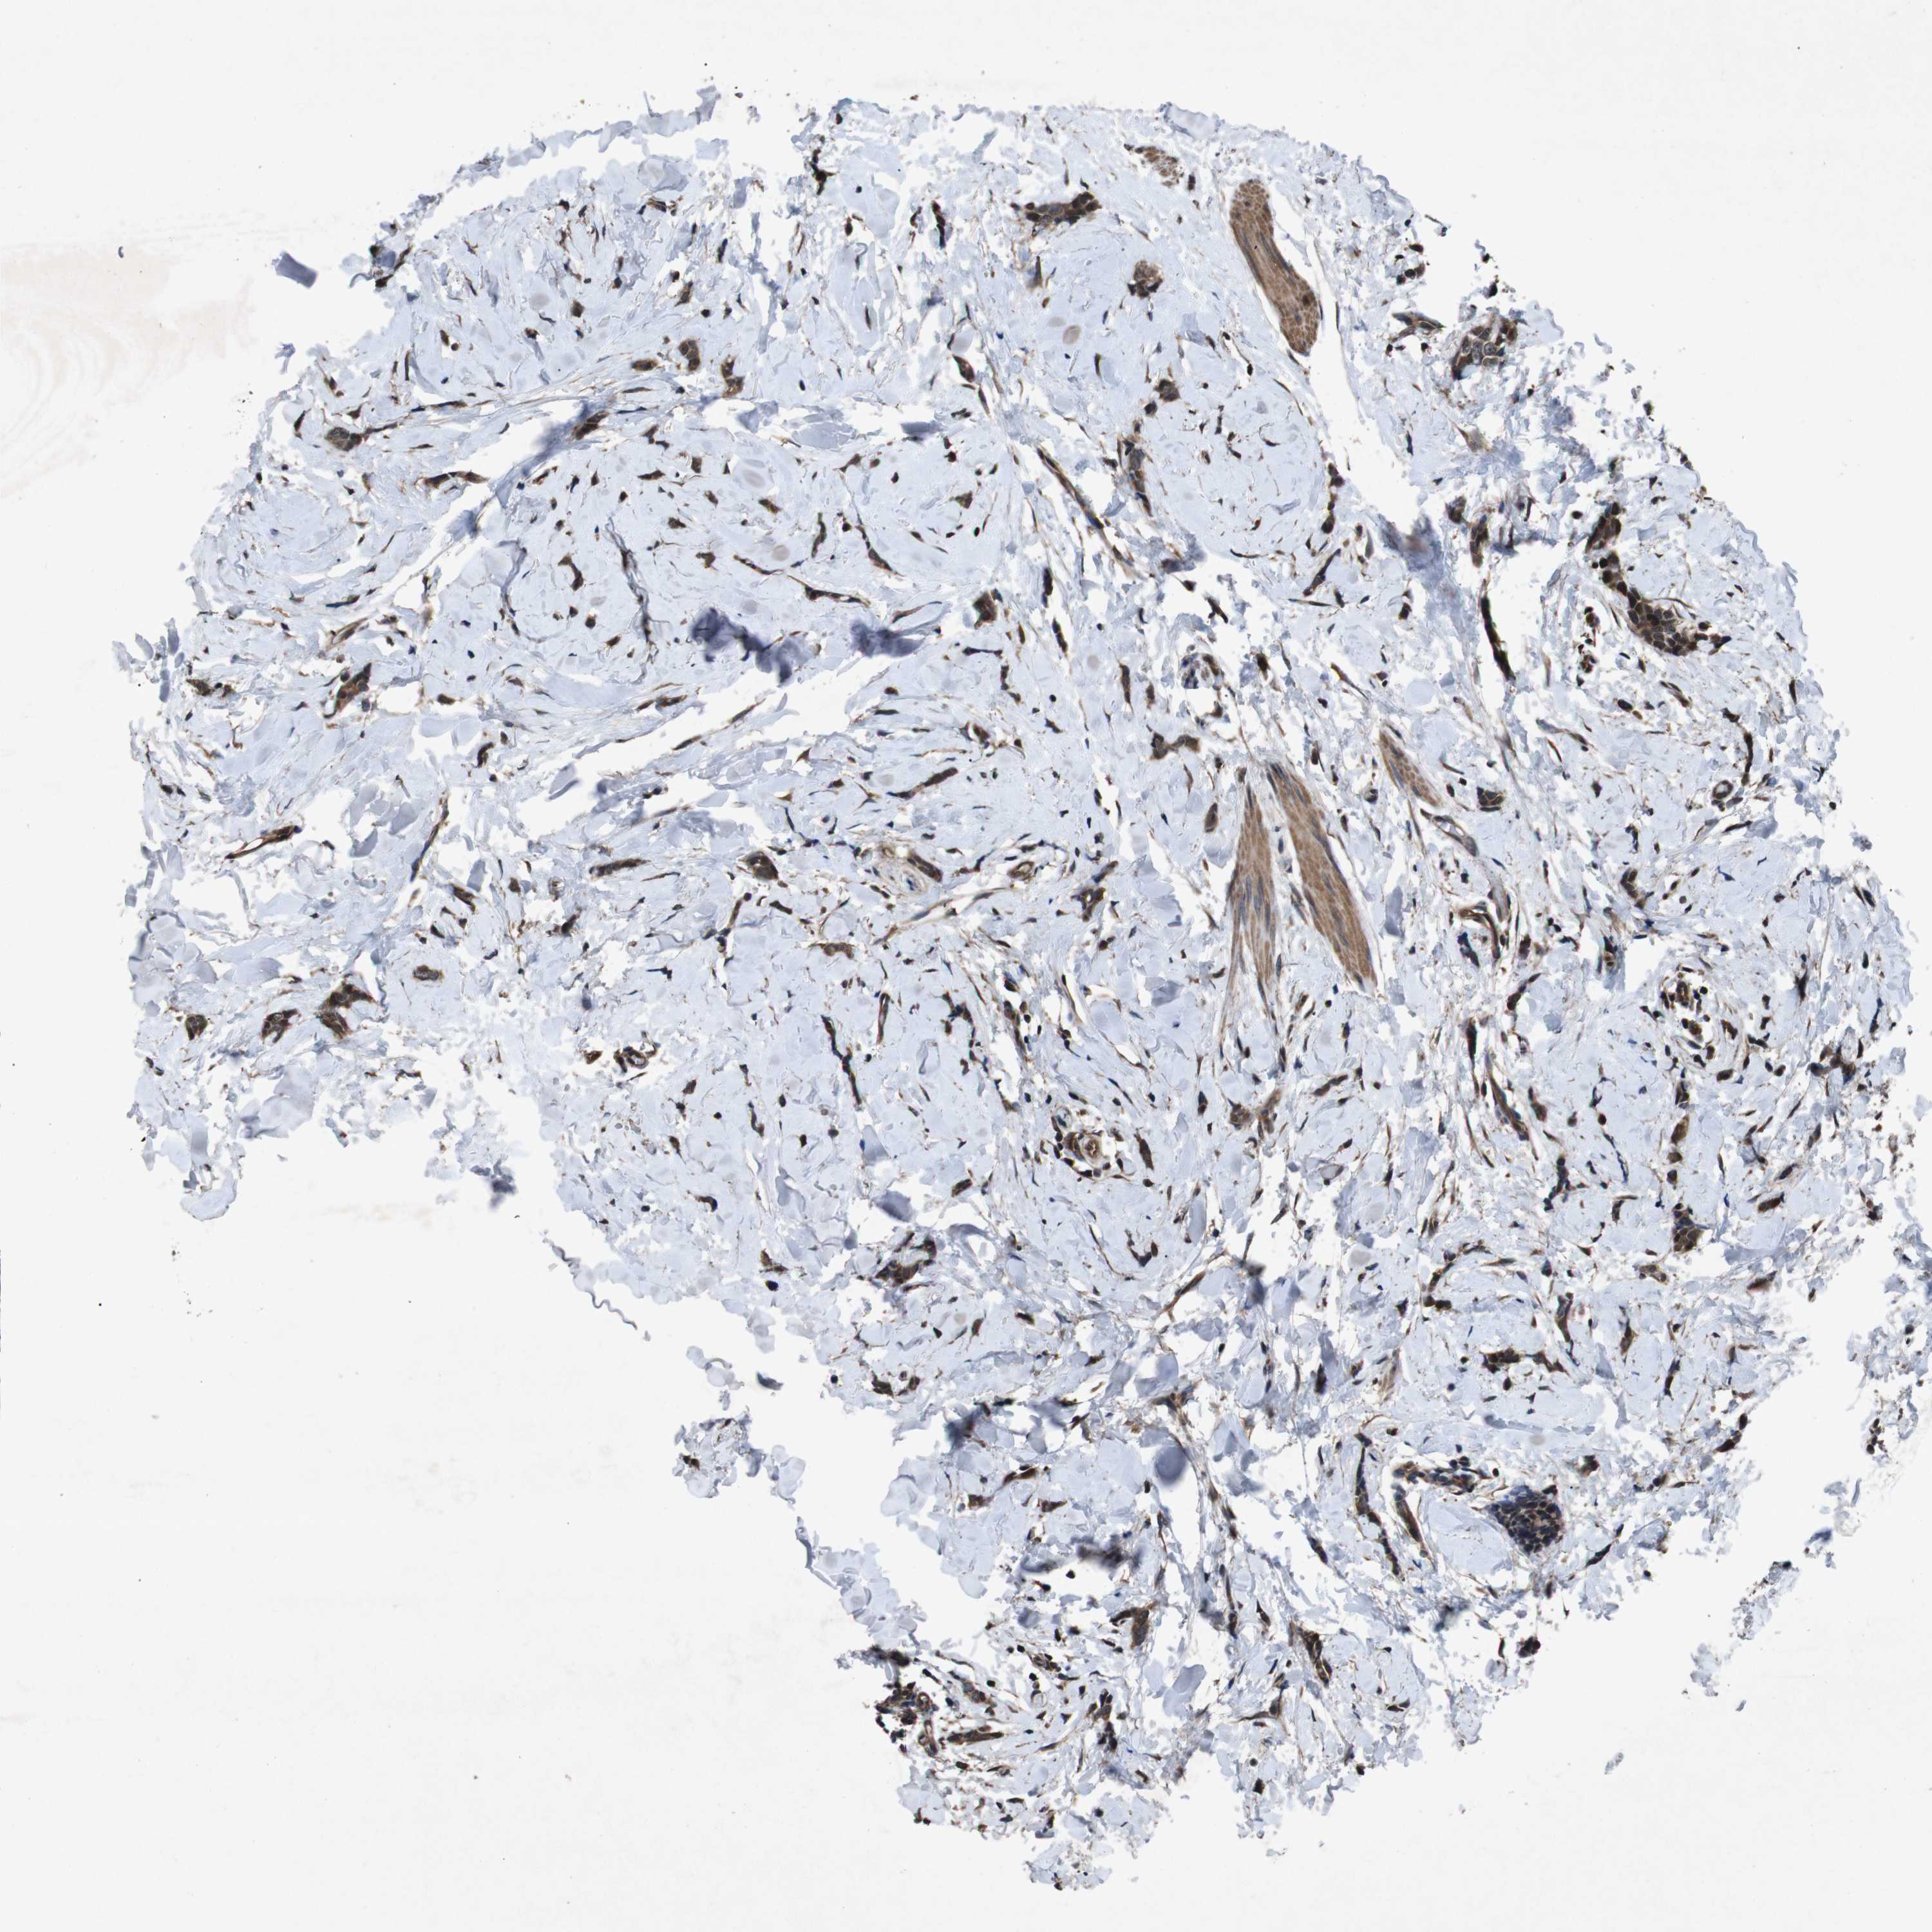

BRCA TCGA BRCA VALIDATION PROTEIN EXPRESSION

ANTIBODIES

AND

VALIDATION